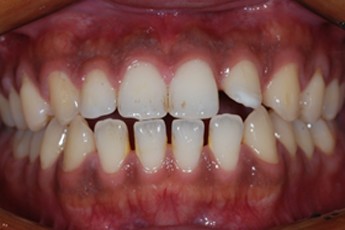

Before

After

- 덧니교정